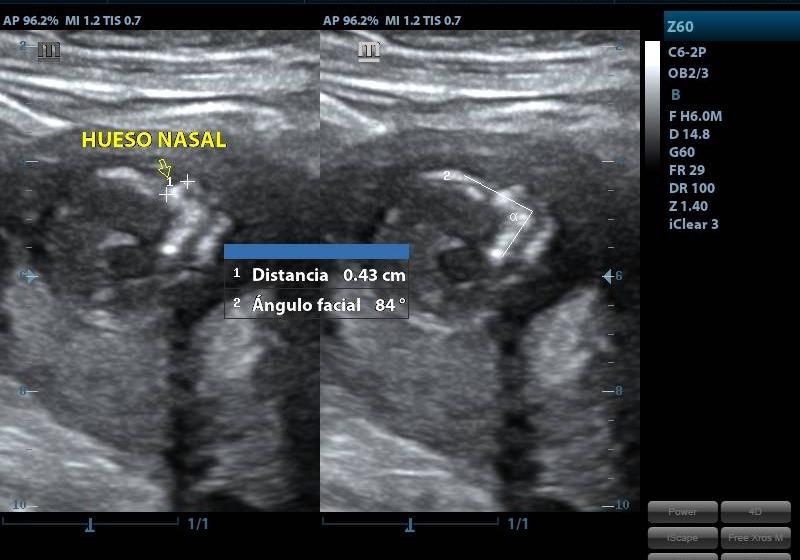

CONDICIÓNINDICACIONES: SE REALIZA ENTRE LAS 12 Y 13 SEMANAS CON 6 DIAS DE GESTACION.

ESPECIFICACIONESLONGITUD DEL FETO CORONOCAUDAL (LCC) LIQUIDO AMNIOTICO FRECUENCIA CARDIACA FETAL (LCF) DESCARTAR CROMOSOMOPATIAS MEDICION TRANSLUCENCIA NUCAL (TN) PRESENCIA Y MEDICION DE HUESO NASAL ANGULO MAXILOFACIAL PARTES FETALES DIAFRAGMA EVALUACION CAMARA CARDIACA EVALUACION COLUMNA VERTEBRAL FLUJOMETRIA DOPPLER ARTERIAS UTERINAS (PREVENTOR PREECLAMPSIA) DUCTUS VENOSO UBICACIÓN DE PLACENTA, DESCARTAR HEMATOMAS O DESPRENDIIENTOS INSERCION DE CORDON UMBILICAL